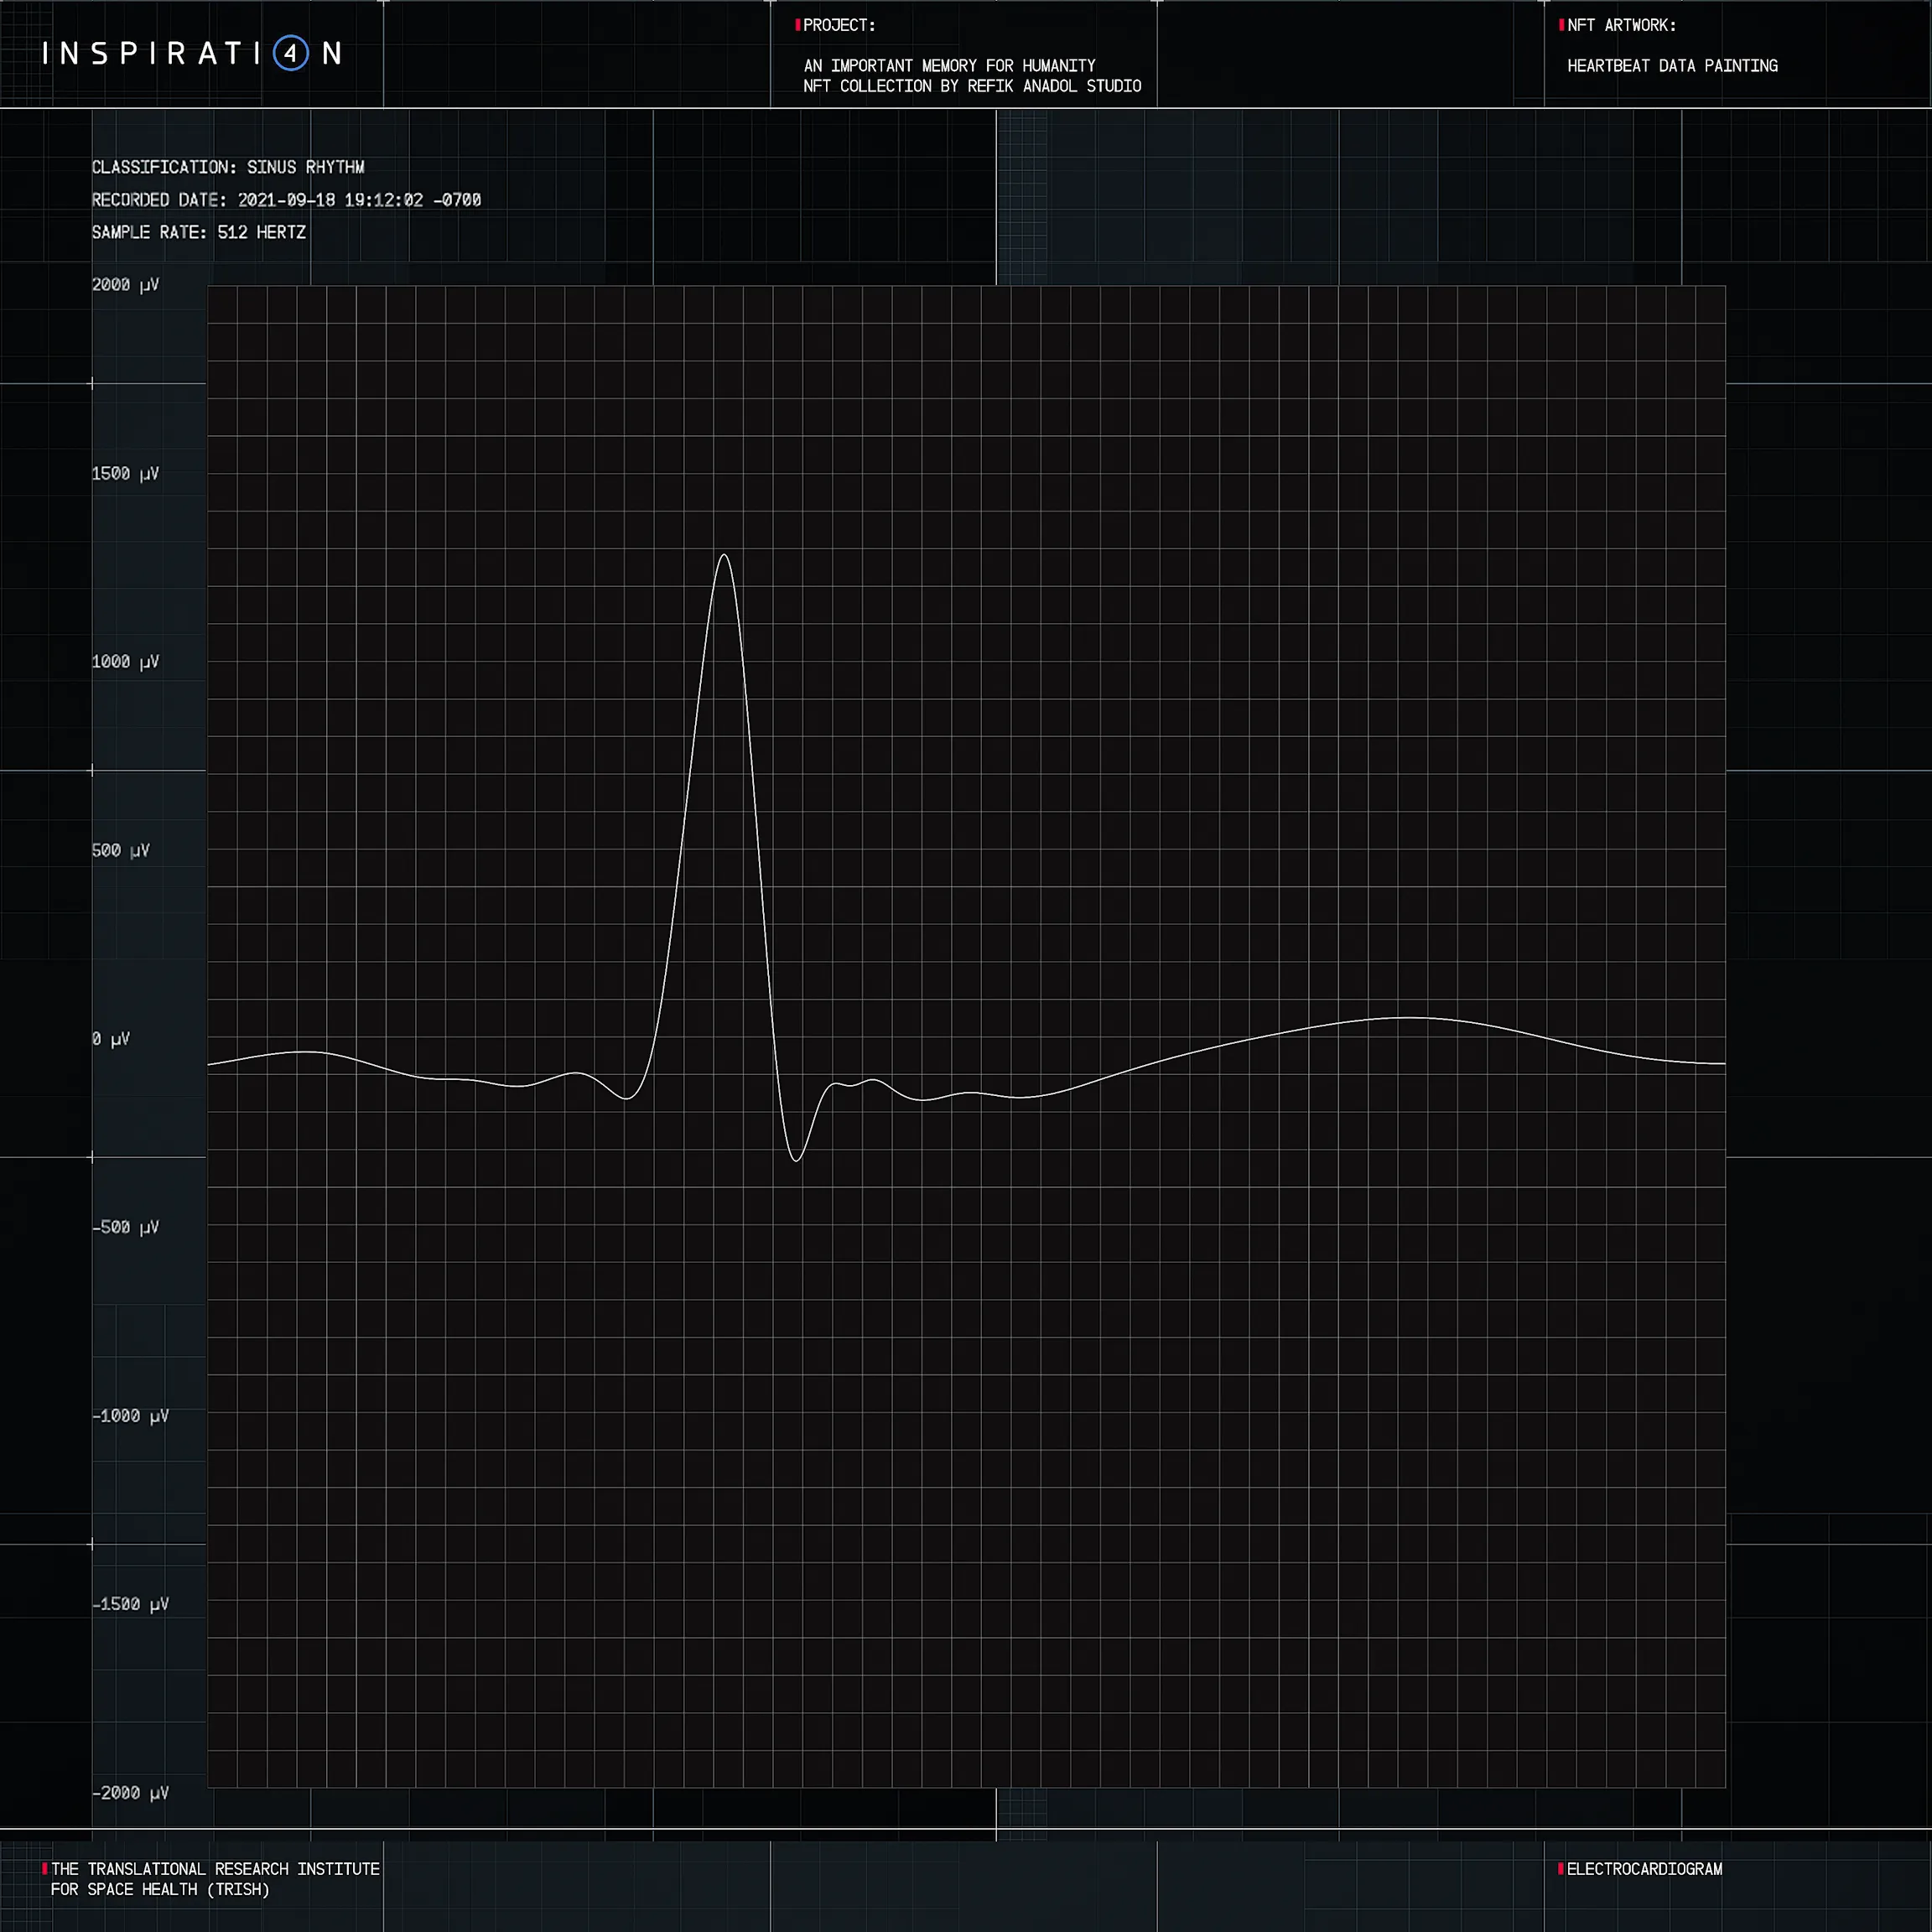

Refik Anadol

HEARTBEAT DATA PAINTING #671

Ξ0.051